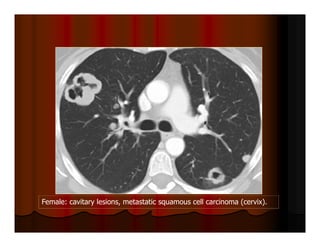

Female: cavitary lesions, metastatic squamous cell carcinoma (cervix).

Female: cavitary lesions,metastatic squamous cell carcinoma (cervix).